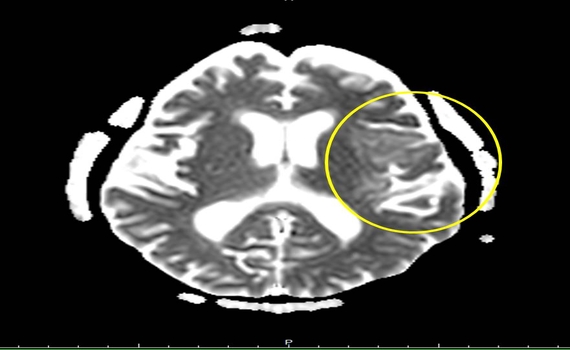

▲腦部核磁共振檢查診斷出腦炎狀況。

(圖/豐原醫院提供)

未料;出院後一週病人感覺不適、意識改變、不明原因發生癲癇,立即送醫,收治神經外科加護病房進行插管治療,並安排腦部核磁共振檢查診斷為腦炎及腰椎穿刺檢查採集腦脊髓液送檢驗,檢驗結果為第一型單純皰疹病毒感染,會同感染科主任黃駟榮醫師使用抗病毒藥物治療,治療後病人從意識昏迷、無法溝通,恢復到可以做簡單溝通、恢復狀況良好,讓家人感到欣慰。